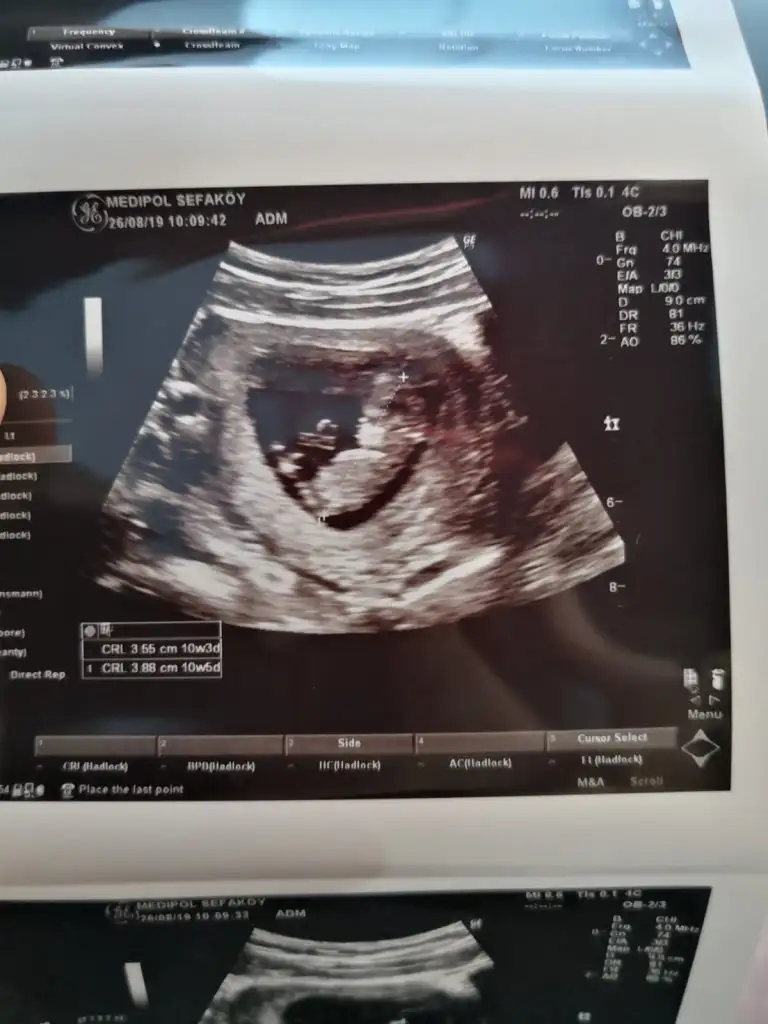

ErkekSelam kızlar. 10+5 günlük hamileyim, var mı bi tahminleriniz

Net olmamakla birlikte kız başka usg varsa paylaşın

Bunda hic belli değil bence ama birde bu var :) yinede tesekkur ederimNet olmamakla birlikte kız başka usg varsa paylaşın

KızBunda hic belli değil bence ama birde bu var :) yinede tesekkur ederim

Sağolun bir kızım var bir kizim daha olsun uzulmem yeterki saglikli olsun :)

Gönlünüzdeki saglıkla olsun inşallah benimki tahminSağolun bir kızım var bir kizim daha olsun uzulmem yeterki saglikli olsun :)